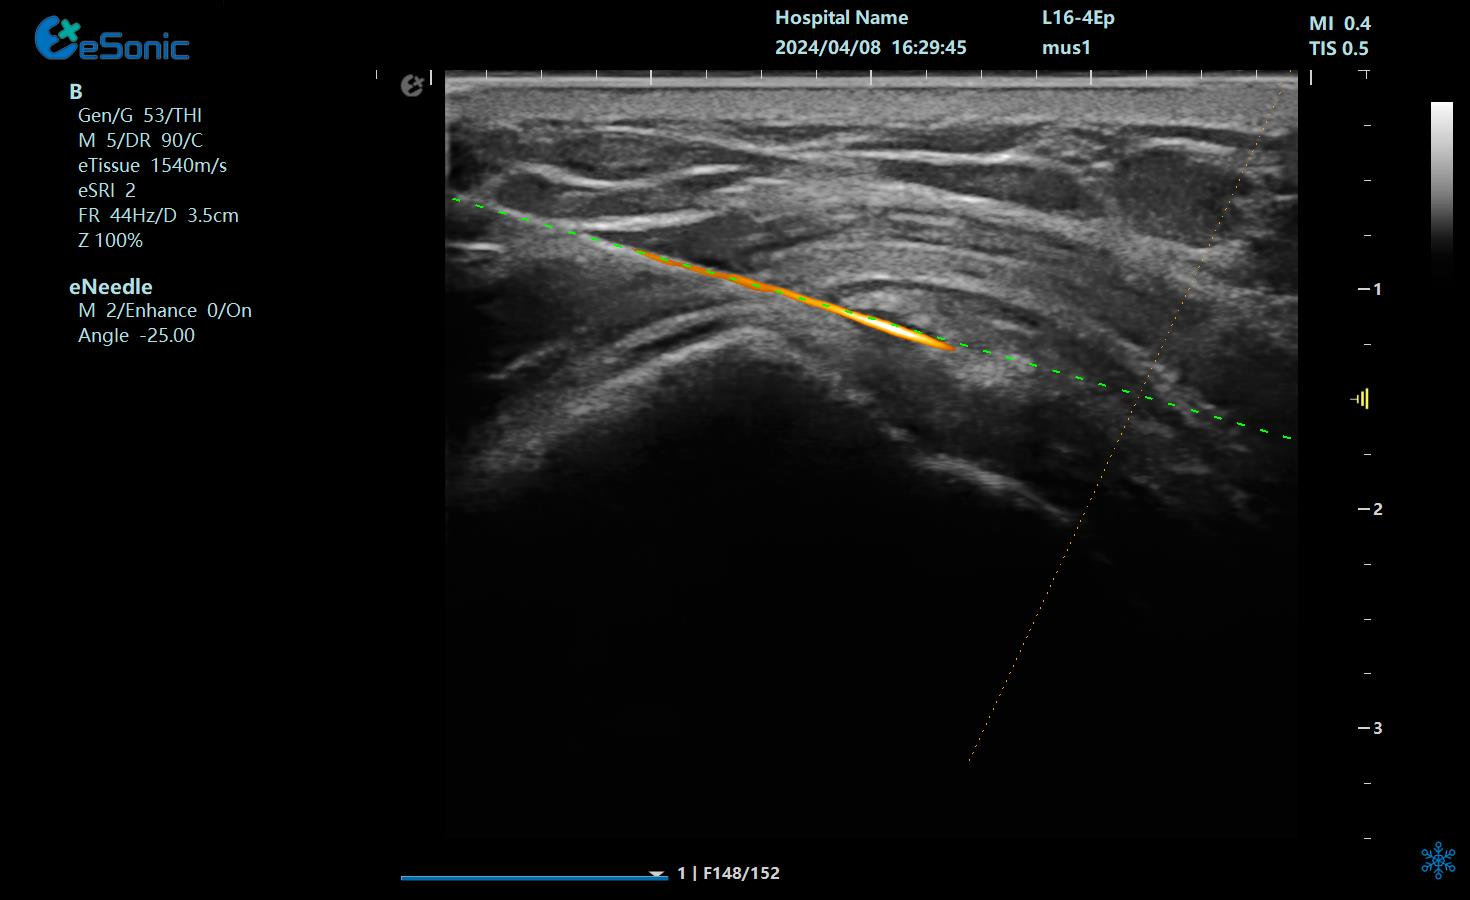

在超声图像中,穿刺针和钙化灶的显示都为强回声,常规的超声引导穿刺即使增强了穿刺针的显示仍不能有效地区分针尖和钙化灶,可能导致对穿刺部位的判断失误,往往比较依赖于医生的经验穿刺到钙化灶。

“Needle TsTM”登场新技术“秒 杀”钙化灶

银河官网医疗(ESI)Needle TsTM穿刺介入智能解决方案物理外挂三连:

1?? ?染色暴击?:给穿刺针穿上"荧光赛博战衣"(智能Map一键上色),钙化灶当场被标记成"通缉犯",超声屏秒变科幻大片!

2?? ?导航开挂?:针尖偏转0.1°?无磁导航立刻甩出"激光瞄准镜",实时画出钙化灶的投降路线图!

3?? ?精准降维?:针头化身"抽钙吸尘器",突突两下吸走顽固钙盐,手术时间比煮泡面还快!

治疗中使用穿刺针智能Map和无磁导航技术